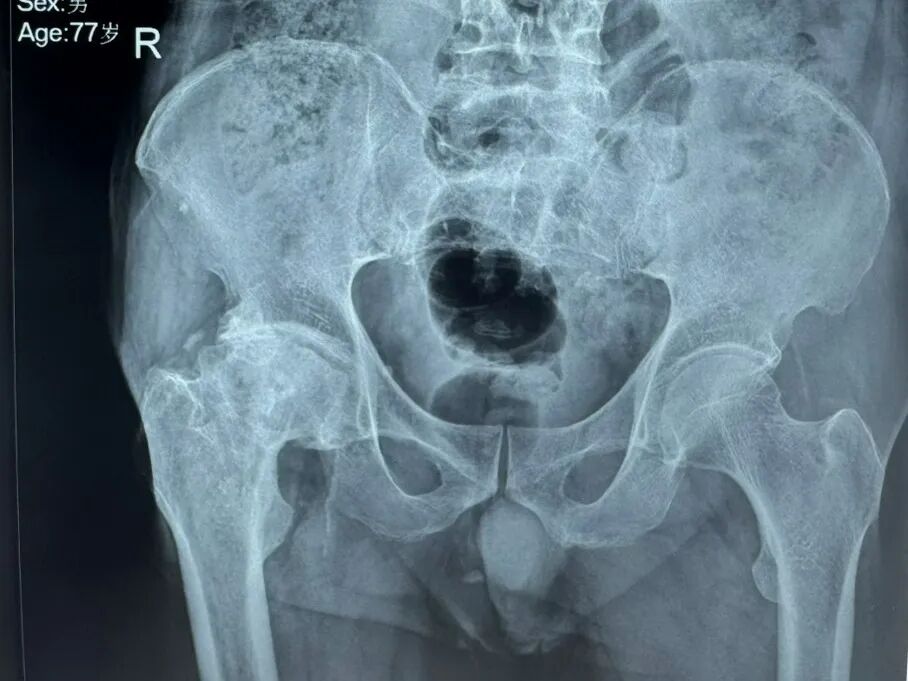

近日,陕西中医药大学附属医院骨伤医院骨病病区成功为一位78岁高龄、曾经历髋部手术的患者完成直接前方入路(DAA)微创全髋关节置换术。该患者王大爷三十年前因股骨颈骨折导致股骨头坏死,此次手术面临髋关节严重骨赘增生、患肢短缩及肌肉组织黏连等复杂情况,属于临床中较为棘手的高龄二次翻修病例。